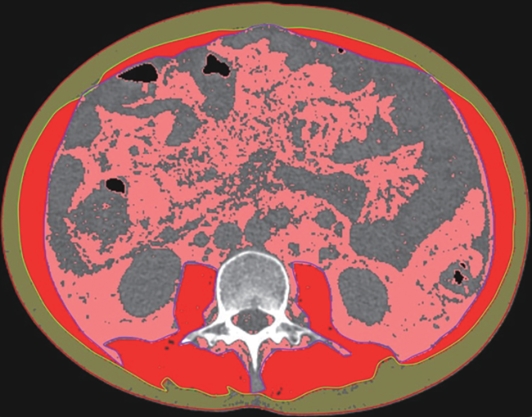

Value of internal stratification analysis of abdominal wall muscles in predicting complications after orthotopic liver transplantation

Xin SHI, Chongxiao LIANG, Bei ZHANG, Jiping WANG

2025, 41(2): 314-321. DOI: 10.12449/JCH250218

Abstract(738) HTML (351) PDF (3265KB)(53)

Abstract:

Objective  To divide the muscle into different subzones according to different density ranges using the stratified analysis on the basis of myosteatosis, and to investigate the effect of muscle density changes on complications (Clavien-Dindo grade ≥Ⅲ) after orthotopic liver transplantation (OLT).  Methods  A retrospective analysis was performed for the medical records of 145 patients who underwent OLT in The First Hospital of Jilin University from May 2013 to September 2020, and with the plain CT scan images of the largest level of lumbar 3 vertebrae of each patient as the original data, Neusoft Fatanalysis software was used to measure related muscle parameters. The independent-samples t test was used for comparison of normally distributed continuous data between two groups, and the Mann-Whitney U test was used for comparison of non-normally distributed continuous data between two groups. The chi-square test or Fisher test was for comparison of categorical data between two groups. RIAS software was used to extract clinical features and perform analysis and modeling, and three machine learning models of logistic regression (LR), support vector machine (SVM), and random forest (RFC) were constructed. The receiver operating characteristic (ROC) curve, the calibration curve, and the decision curve were plotted for each model to calculate the area under the ROC curve (AUC), sensitivity, specificity, precision, F1 score, and accuracy.  Results  The three machine learning models of LR-C, SVM-C, and RFC-C were established based on the 7 clinical features before muscle stratification analysis, among which the RFC-C model had an AUC of 0.803, a sensitivity of 0.588, and a specificity of 0.778 in the test set. Among the models of LR-CS, SVM-CS, and RFC-CS established based on the 16 clinical features after muscle stratification analysis, the LR-CS and SVM-CS models had an AUC of 0.852 in the test set, with a sensitivity of 0.765 and 0.706, respectively, and a specificity of 0.889 and 0.926, respectively. Comparison of the AUC, sensitivity, specificity, precision, F1 score, and accuracy of each model in the test set before and after muscle stratification analysis showed that there were improvements in the parameters of the predictive model after muscle stratification analysis. Comparison of the decision curves and calibration curves of each predictive model showed that the LR-CS and SVM-CS models had good efficacy in predicting postoperative complications (Clavien-Dindo grade≥Ⅲ) in OLT patients.  Conclusion  On the basis of myosteatosis, the division of the muscle into different subzones according to different densities using the stratified analysis has a certain value in predicting postoperative complications in patients with OLT.